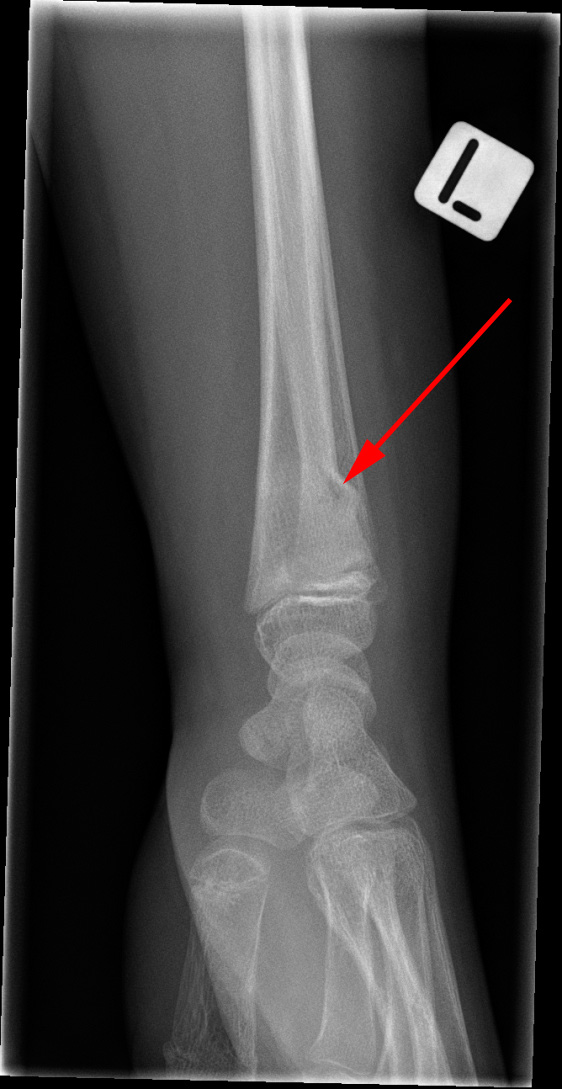

Røntgenundersøgelse af venstre hånd viser en såkaldt green-stick brud (rød pil) hos en yngre person.